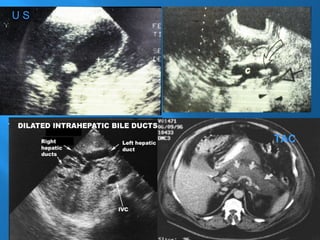

1.- Ultra Sonografía (US) Es el Standard de

Oro (Hígado,Vesícula,V.Biliares y Páncreas)

Ultrasonografía

U S